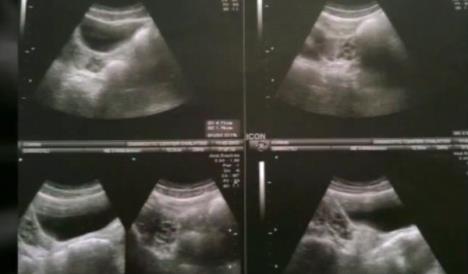

Džoana Dženola ima 27 godina, a zbog medicinskog sindroma s kojim je rođena ona nema maternicu, cerviks - odnosno grlić, kao ni gornji deo vagine.

Taj sindrom pogađa jednu od 5.000 žena, a u želji da otkloni predrasude o ovom poremećaju, podelila je svoju ispovest.